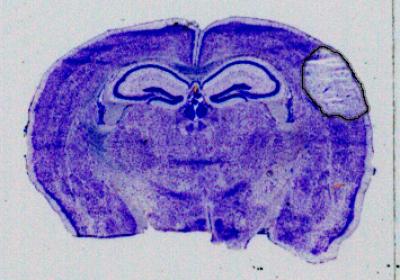

In a study published today in the Journal of Experimental Medicine , researchers successfully used a new approach that significantly minimized brain damage caused by stroke in mouse models. The new approach works by targeting hemichannels--pathways that allow for the flow of chemical ions and small molecules--that are expressed by astrocytes, cells that play a protective role for neurons in the brain.

For the study, the researchers used a genetic approach that mutated the channel proteins, called connexins, in such a way that blocks the formation of hemichannels. This allows the astrocytes to protect the neurons, significantly reducing the size of the stroke injury in the brain. The researchers also used a molecule called Gap19 to block the hemichannels, in the same stroke model, which also resulted in smaller stroke damage. Together, the two approaches demonstrate that connexin hemichannel blockers could be used as a neuroprotective agent in stroke.